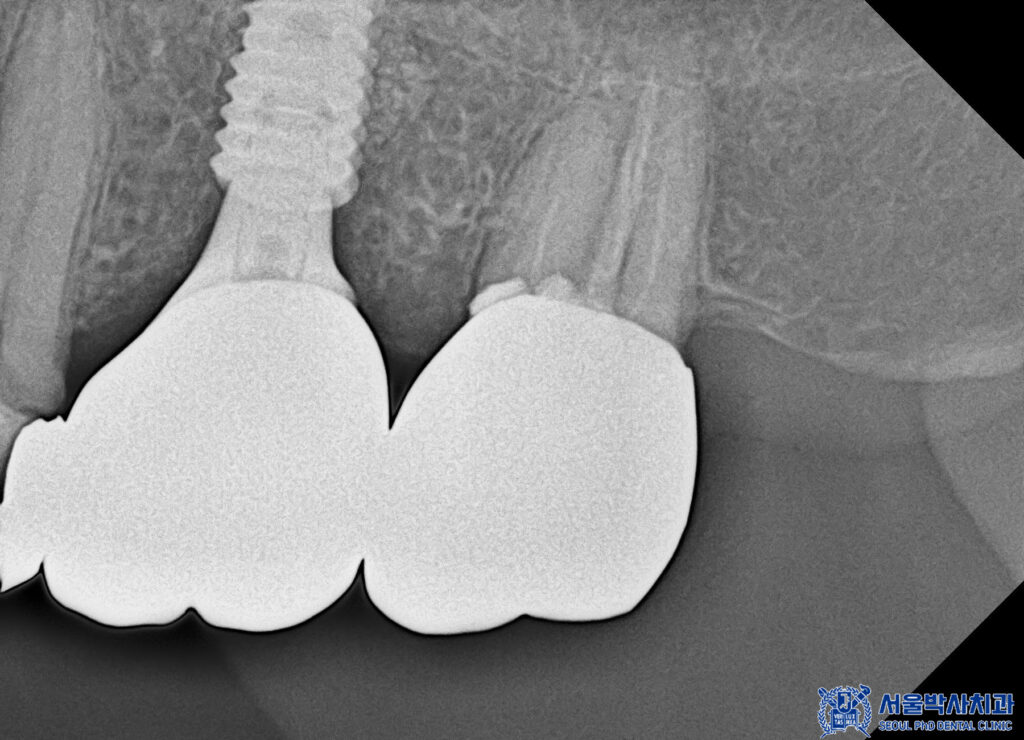

그래서 먼저 왼쪽 아래 상실된 부분의

무절개임플란트 3개를 식립 하기로

계획을 수립하였습니다.

무절개 임플란트

3개 식립을 진행했습니다.

최소침습 방식으로 임플란트를 식립 하여

절개 부위가 적고

출혈도 적었습니다.

본을 뜬 후 맞춤형 지대주를 제작하고,

그에 맞는 보철물을 제작하여

교합과 형태, 색상까지

세심하게 조정했습니다.

이렇게 정밀하게 작업된 보철물은

자연스러운 느낌을 주며,

환자분의 편안한 씹는 기능을

지원할 수 있도록

설계되었습니다.